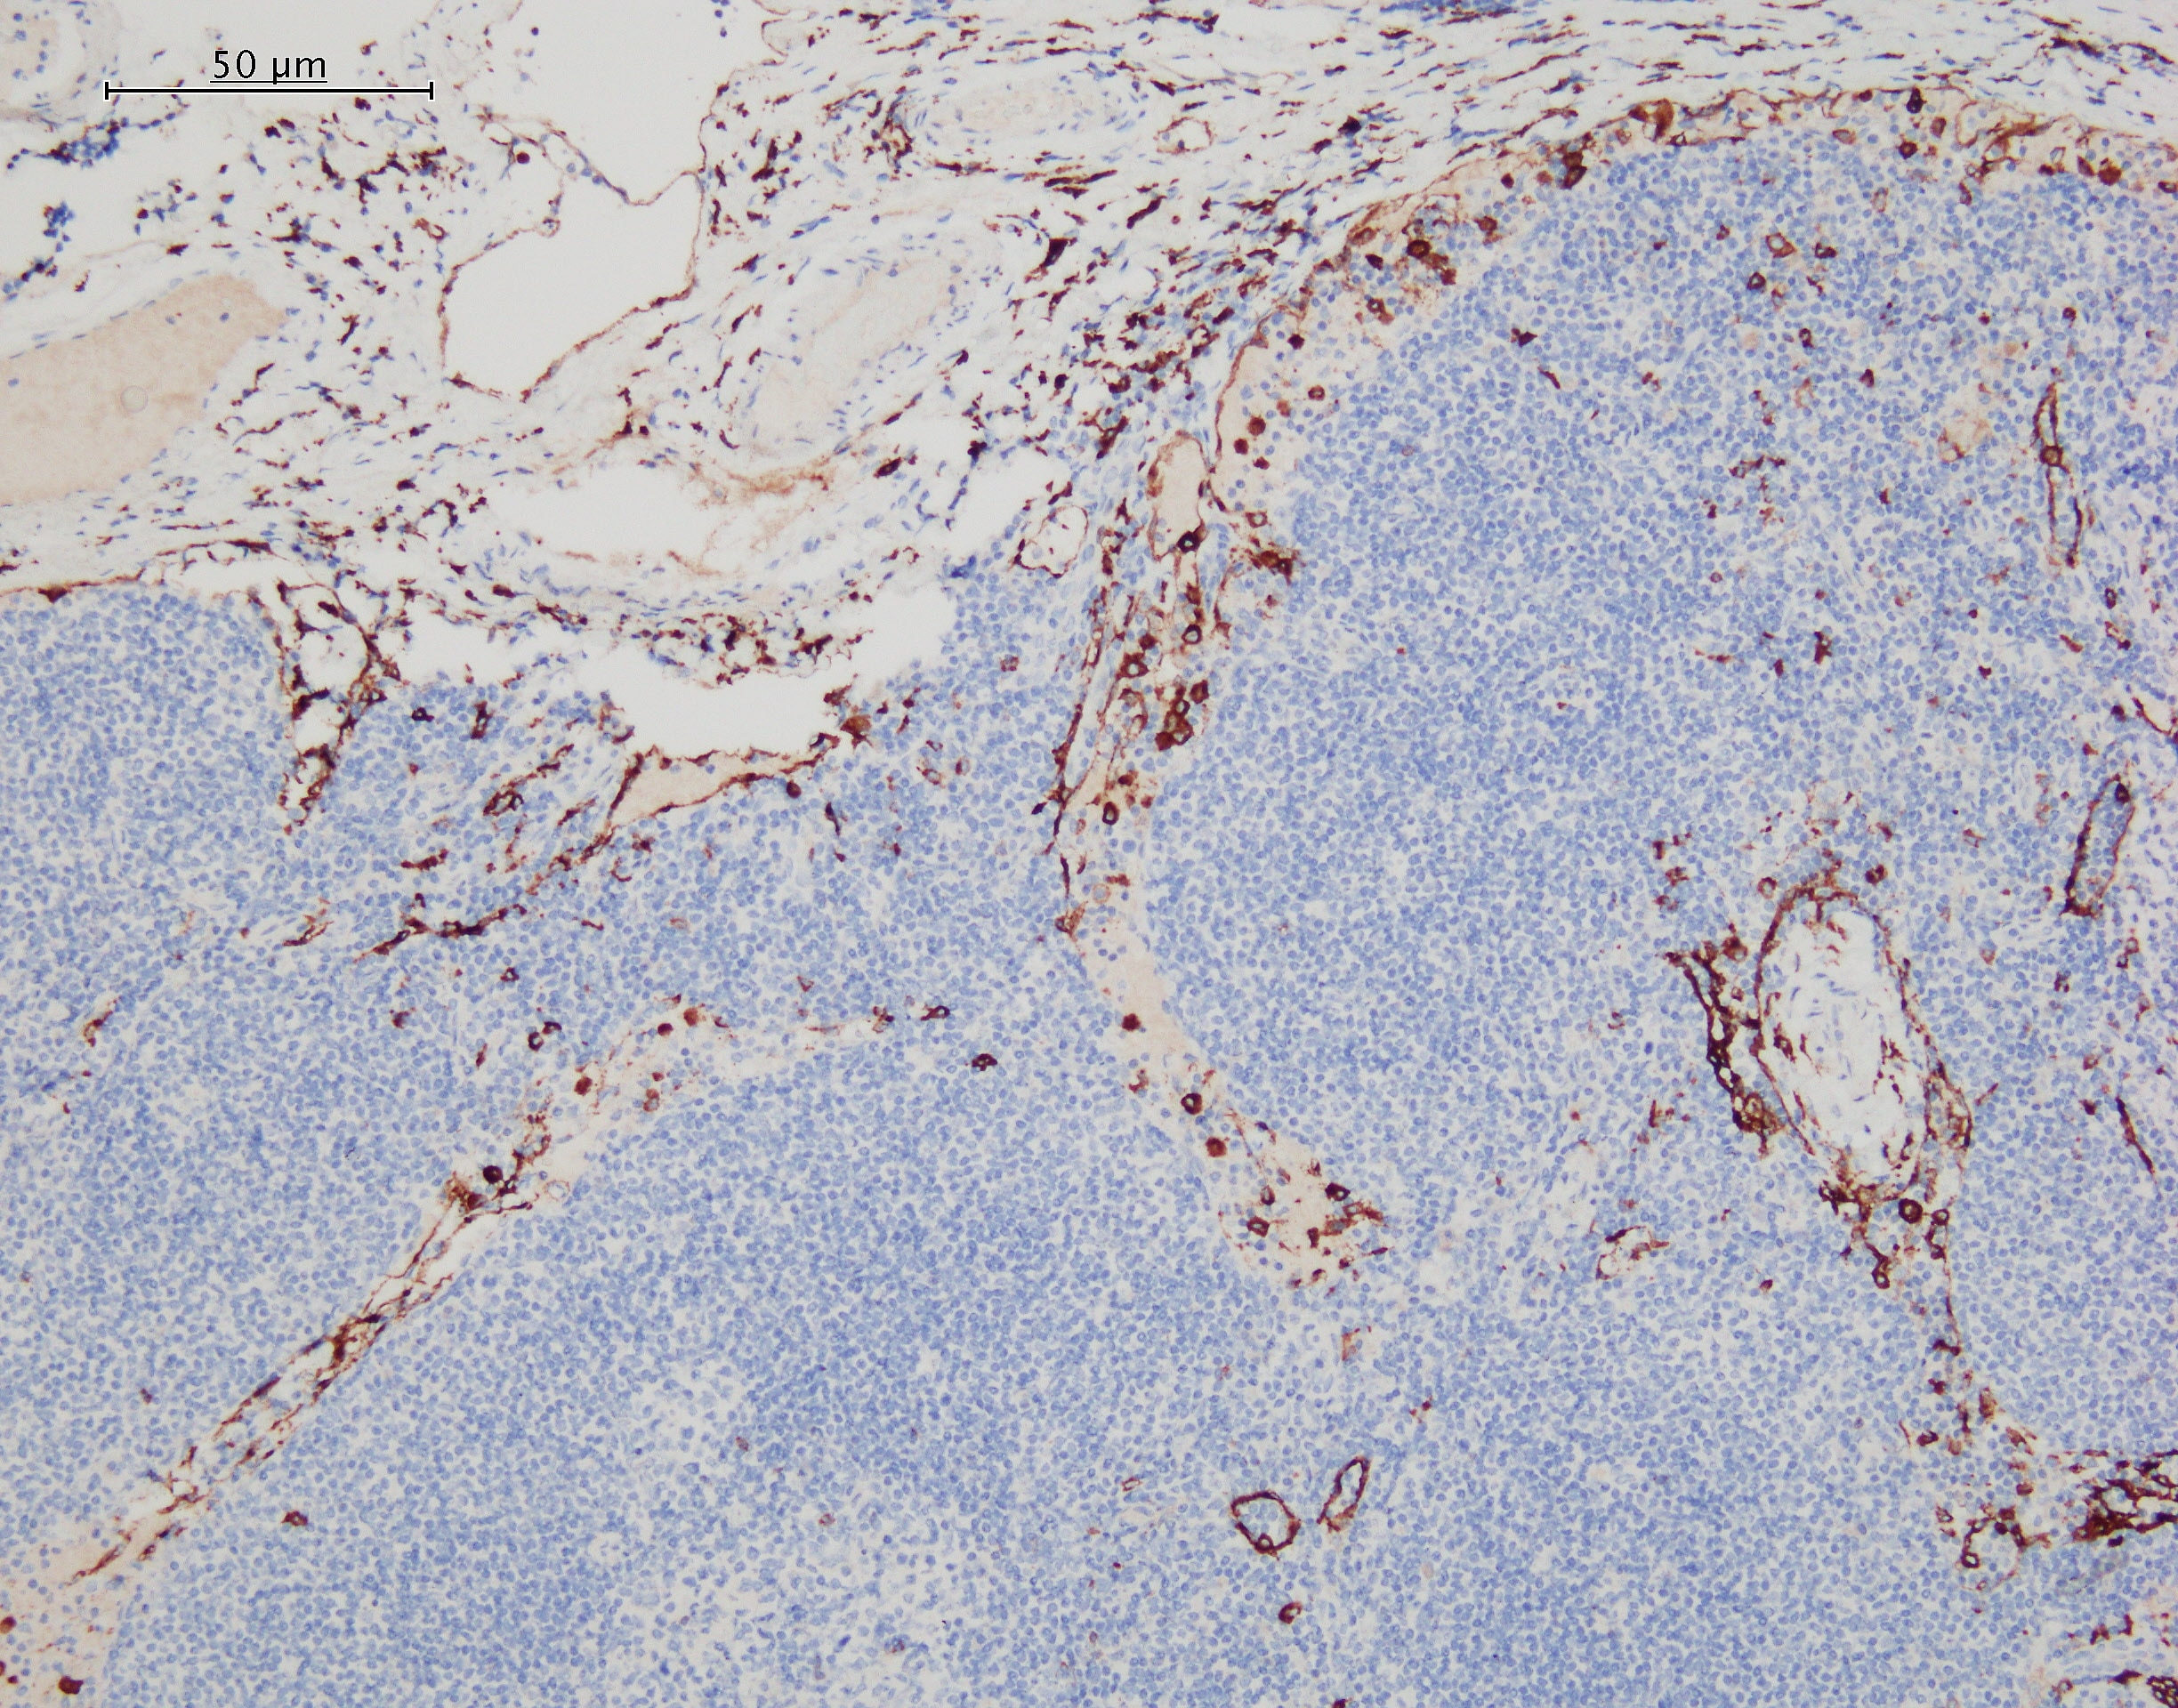

MMR/CD206 in Human Liver. MMR/CD206 was detected in immersion fixed paraffin-embedded sections of human liver using Mouse Anti-Human MMR/CD206 Monoclonal Antibody (Catalog # MAB25341) at 15 µg/mL overnight at 4 °C. Before incubation with the primary antibody, tissue was subjected to heat-induced epitope retrieval using Antigen Retrieval Reagent-Basic (Catalog # CTS013). Tissue was stained using the Anti-Mouse HRP-DAB Cell & Tissue Staining Kit (brown; Catalog # CTS002) and counterstained with hematoxylin (blue). Specific staining was localized to endothelial cells in sinusoids. View our protocol for Chromogenic IHC Staining of Paraffin-embedded Tissue Sections.